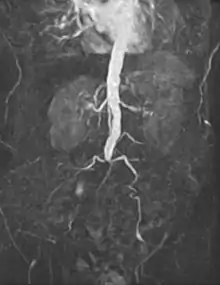

Infrarenal aortic occlusion imaged with magnetic resonance angiography (MRA).

The management of arterial pathology excluding coronary and intracranial disease is within the scope of vascular surgeons. Disease states generally arise from narrowing of the arterial system known as stenosis or abnormal dilation referred to as an aneurysm. There are multiple mechanisms by which the arterial lumen can narrow, the most common of which is atherosclerosis.[7] Symptomatic stenosis may also result from a complication of arterial dissection. Other less common causes of stenosis include fibromuscular dysplasia, radiation induced fibrosis or cystic adventitial disease. Dilation of an artery which retains histologic layers is called an aneurysm. An aneurysms can be fusiform (concentric dilation), saccular (outpouching) or a combination of the two. Arterial dilation which does not contain three histologic layers is considered a pseudoaneurysm. Additionally, there are a number of congenital vascular anomalies which lead to symptomatic disease that are managed by the vascular surgeon, a few of which include aberrant subclavian artery, popliteal artery entrapment syndrome or persistent sciatic artery.[8] Vascular surgeons treat arterial diseases with a range of therapies including lifestyle modification, medications, endovascular therapy and surgery.